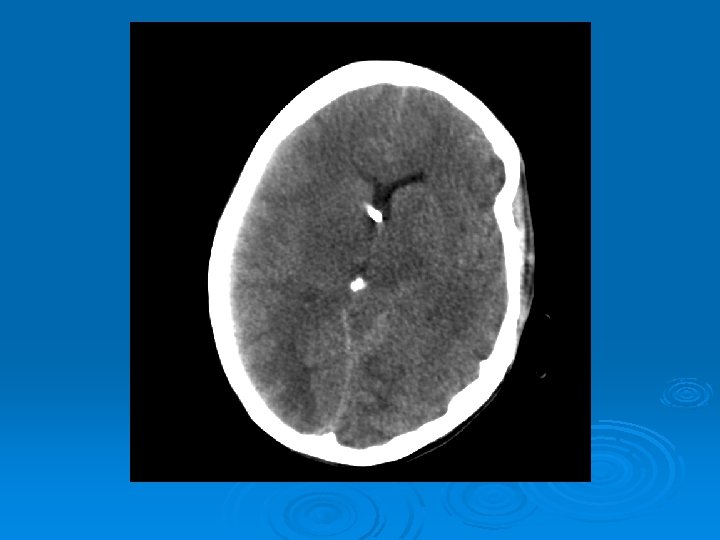

Course: Ø 3 PM, RN noticed anisocoria and L pupil non-reactive. Ø Neurology STAT dose mannitol and w/ dilantin. Ø Pt went for stat head Ct:

CT head 2/11/07 Ø A right frontal ventriculostomy catheter Ø Diffuse sulcal effacement with thickening of the cortex. Ø Loss of gray-white differentiation and hypodensity in the left parietooccipital region. Ø There is diffuse hypodensity of the cerebellum and brainstem. Ø Ø Ø The basilar cisterns are nearly completely effaced. Ø Impression: Ø Worsened diffuse cerebral edema The lateral ventricles are smaller

Course: Ø Neurosurgery saw pt: on exam she had lost cough, gag reflexes, corneal reflexes, she had flexed RUE, semipurposeful with bilateral extended LE. Ø Concern for herniation: placed Ø ICP 35 -40 10 th-11 th EVD